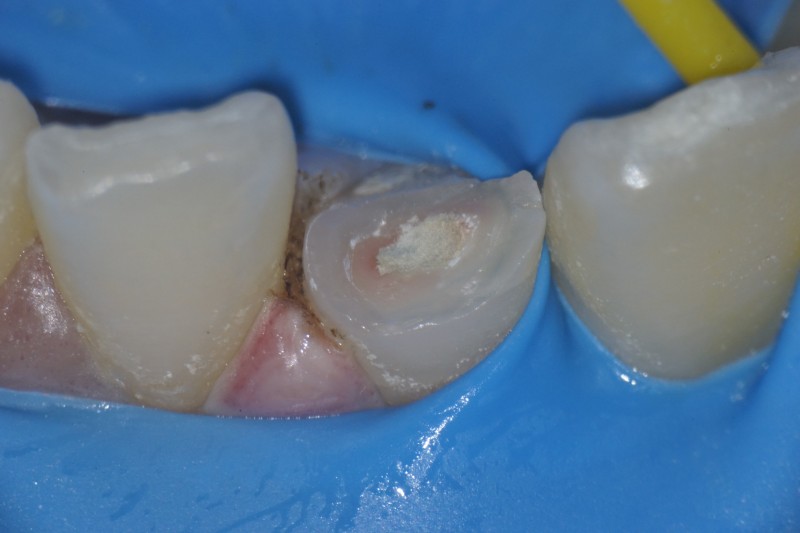

神経が露出しています。

このようなケース、一般的には神経を取ってかぶせ物を入れる治療になると思いますが、神経を取ると歯の寿命は短くなります。

このケースでは、神経を取らずに保存し、詰め物で修復することにしました。

MTAセメントで神経を保護します。